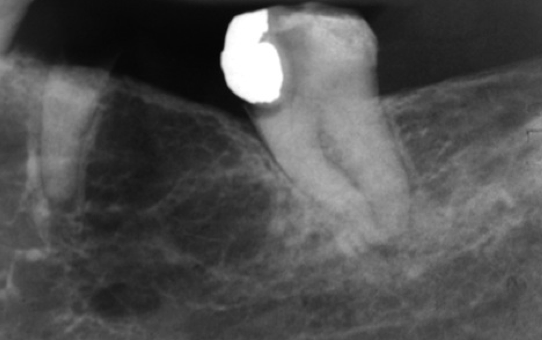

What is the likely Dx?

Focal osteoporotic marrow defect.